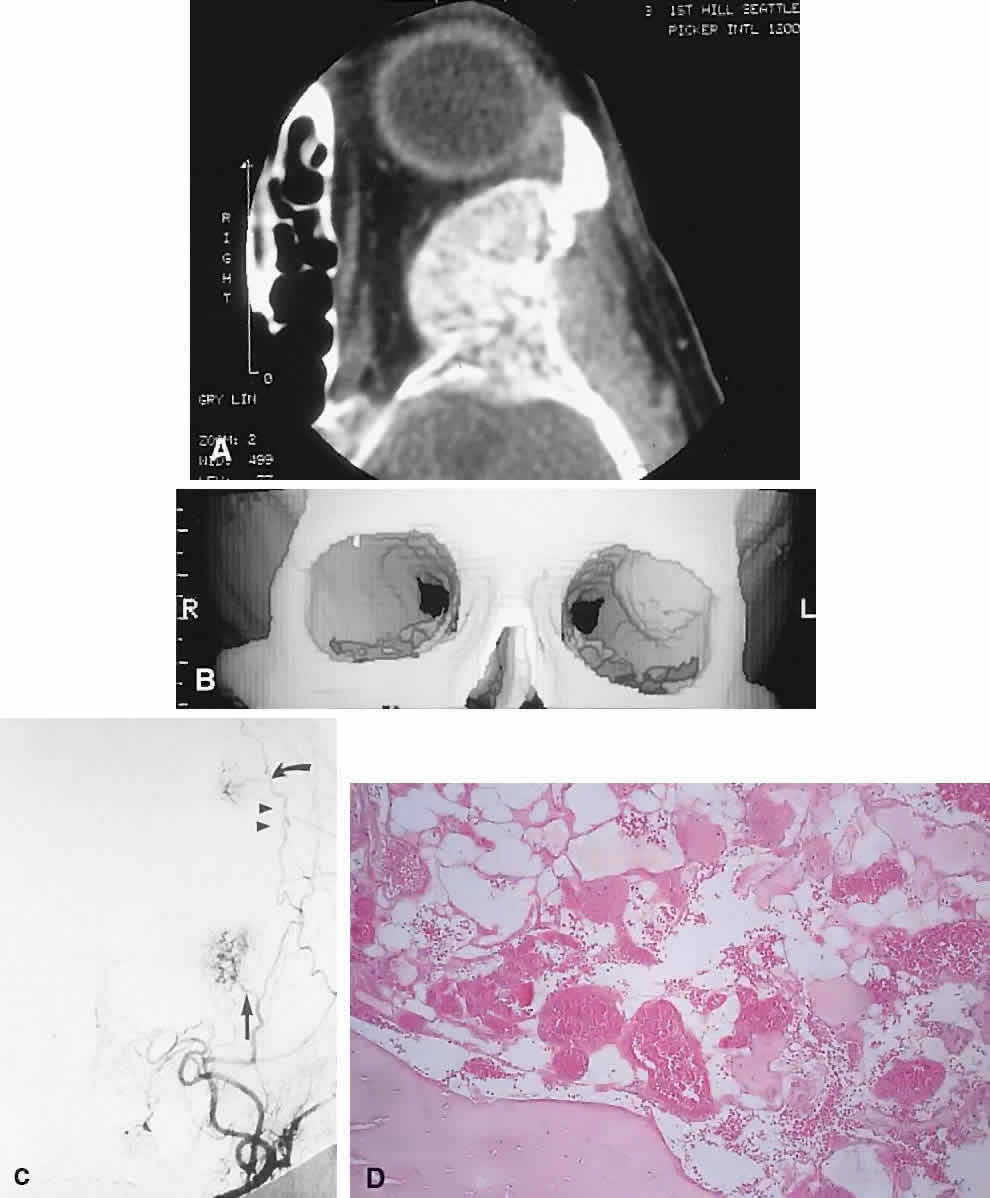

| The above clinical patterns correlate reasonably well with the following